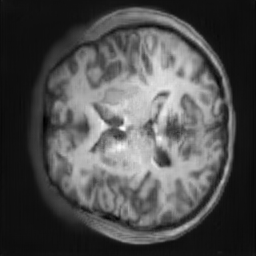

The study utilizes three 3D datasets, namely the GSP dataset[3], the LIDC-IDRI dataset[1], and the dataset employed for the Lung Nodule Analysis 2016 (LUNA16) challenge[21] which is a subset of LIDC-IDRI dataset. Samples from generated images at different stages of training are presented in Fig. 2 and Fig.3.

CRF-GAN synthetic images at different iterations

Refer to caption

20000

30000

40000

50000

60000

70000

80000

HA-GAN synthetic images at different iterations

Figure 2: Synthetic images of CRF-GAN and HA-GAN at different iterations of training on GSP dataset